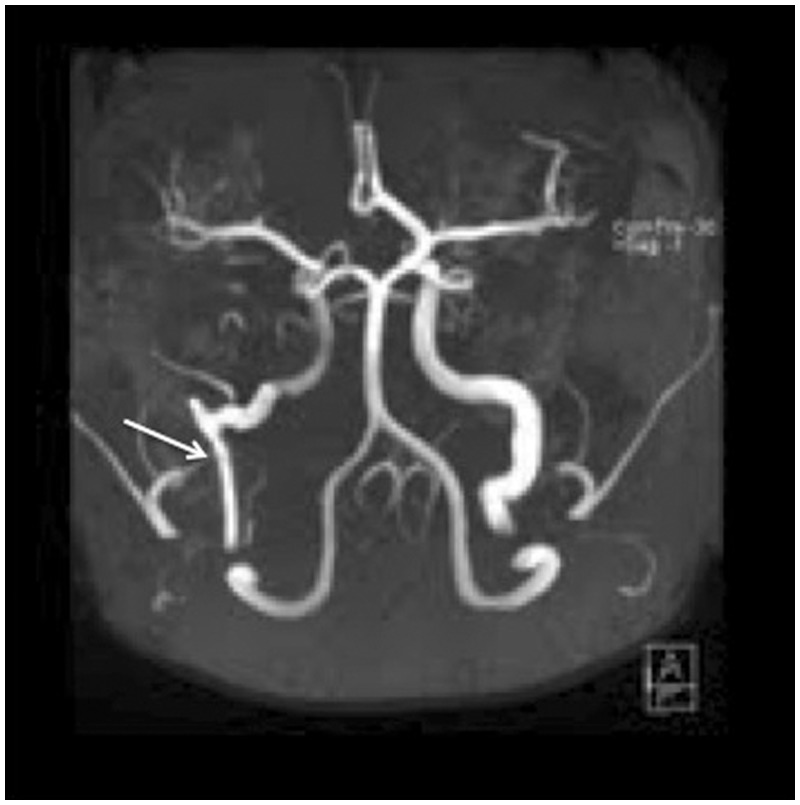

We report a case of a young woman with an aberrant right internal carotid artery (ICA) presenting as a retrotympanic reddish mass. This variant of the ICA represents the collateral pathway that is formed as a result of an embryological agenesis of the cervical segment of the ICA. The embryonic inferior tympanic artery is recruited to bypass the absent carotid segment. This hypertrophied vessel may be seen otoscopically and wrongfully considered to be a vascular middle ear tumor. Informing the otorhinolaryngologist of this important vascular variant not only obviates biopsy but also helps in careful preoperative planning of eventual middle ear procedures.